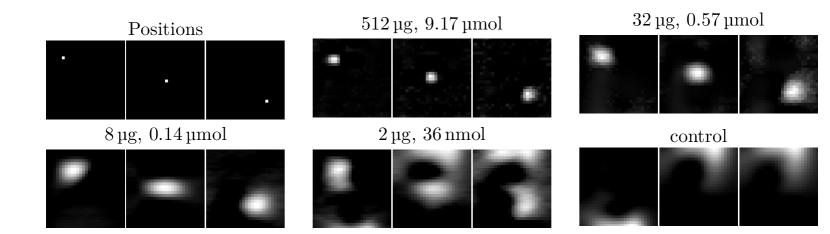

To determine the sensitivity of the imager we used a protocol developed in [4]. First, a dilution series of the tracer Perimag (micromod) was prepared with samples and varying iron mass between and . For each iron mass, the sample was moved to three different positions within the field-of-view (FOV), so that a distinction could be made between the sample signal and reconstruction artefacts. All images were recorded using a 2D imaging sequence. Results of the sensitivity study are shown in Fig. 2. It was possible to detect the sample without artefacts starting from down to . For several artefacts appeared, but the movement from the upper left to the lower right corner was still visible. For (not shown) and the control measurement, no moving sample could be observed. Therefore, the detection limit of the scanner is about iron.

To translate the iron mass into a concentration, we prepared a concentration series and used an ellipsoid (half-axes , and ) filled with different SPIO concentrations. The ellipsoid was filled with to iron in steps leading to concentrations varying between and . To determine the sensitivity limit for the concentration series we used the same experimental protocol as the iron mass study. As can be seen in Fig. 2, it was possible to detect the sample for concentrations starting at down to . For (not shown) and for the control experiment no movement of the sample could be detected. Thus, the detection limit in terms of concentration is about (), which is the lowest iron concentration imaged by MPI so far.